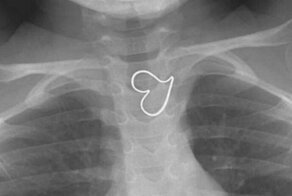

- Трехлетняя девочка проглотила кулон, и удивила врачей "идеальным" рентгеном